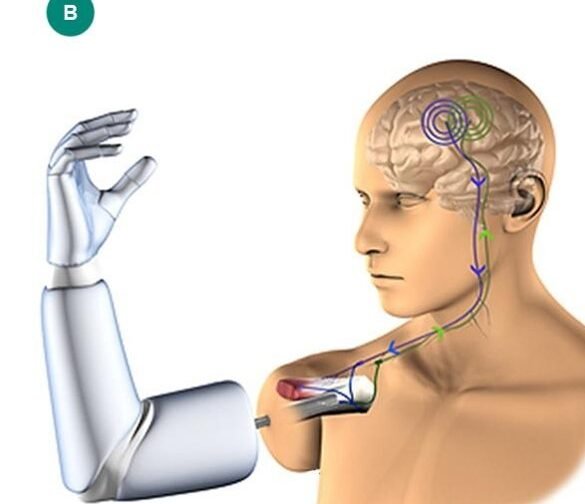

Los avances en tecnología médica han revolucionado el campo de las prótesis, destacando especialmente las prótesis robóticas...